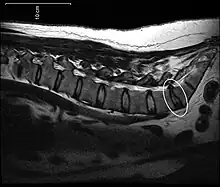

Disc protrusion

A disc protrusion is a medical condition that can occur in some vertebrates, including humans, in which the outermost layers of the anulus fibrosus of the intervertebral discs of the spine are intact but bulge when one or more of the discs are under pressure.

A disc protrusion may progress to a spinal disc herniation, a condition in which there is a tear in the anulus fibrosus.